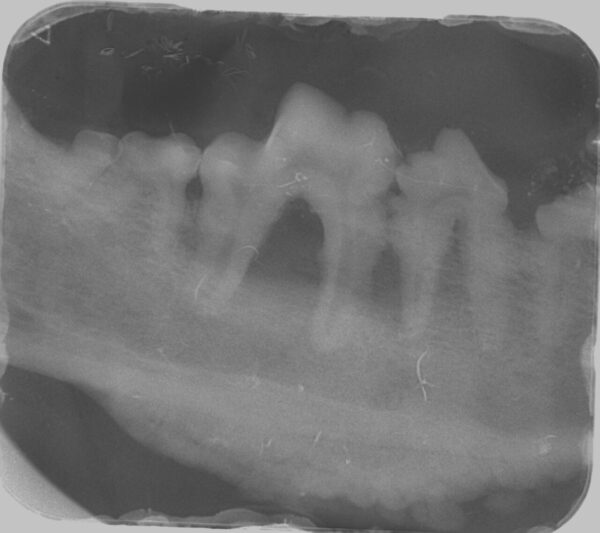

Enfermedad periodontal (EP)

Para el diagnóstico de la EP, además de realizar un examen periodontal a través del sondaje debemos apoyarnos en la radiografía, ya que nos proporciona información acerca de la cantidad de pérdida ósea existente, así como del patrón que sigue esta pérdida (horizontal y/o vertical). En dientes multirradiculares, podemos servirnos de la furca para evaluar la pérdida de hueso, ya que aparecen áreas radiolúcidas bajo la bifurcación radicular a medida que se produce la destrucción ósea.

De acuerdo a esta pérdida del hueso alveolar detectada a nivel radiológico, clasificaremos la EP en cuatro grados:

- Grado 1 (PD1): sin pérdida ósea.

- Grado 2 (PD2): pérdida del soporte óseo menor al 25 % (imagen 7).

- Grado 3 (PD3): pérdida del soporte óseo de un 25-50 % (imagen 8).

- Grado 4 (PD4): pérdida del soporte óseo mayor de un 50 % (imagen 9).

Además de permitirnos evaluar el grado de enfermedad periodontal, también hace posible seleccionar el mejor tratamiento en función de su patología y las posibles complicaciones, como las fracturas mandibulares iatrogénicas en perros de talla pequeña con enfermedad periodontal PD4 (imágenes 10 y 11).